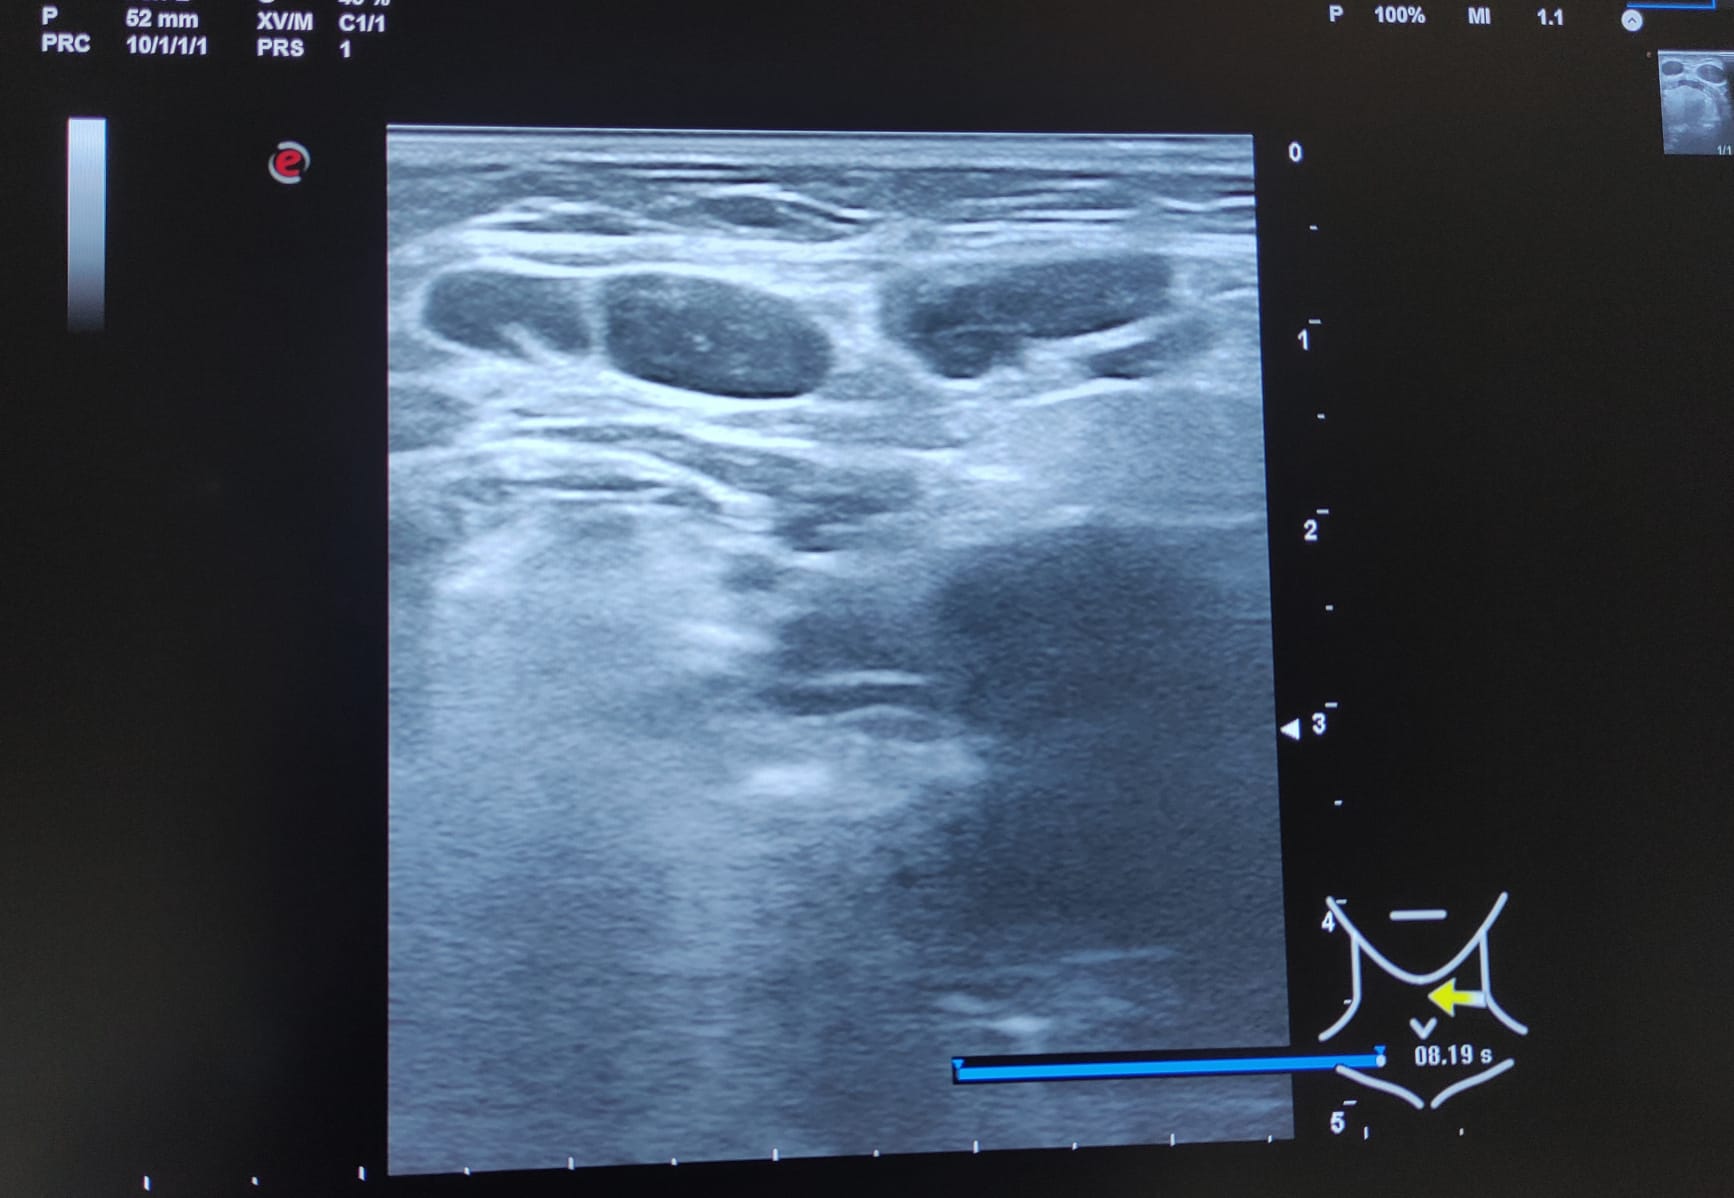

Múltiples adenopatías (más de 12) de varios tamaños siendo la mayor de 2 cm y de morfología redondeada, alguna sin hilio ni centro graso.

A los 3 meses se realiza nueva ecografía sin observar cambios significativos en las adenopatías ya visualizadas. Paciente permanece asintomática.